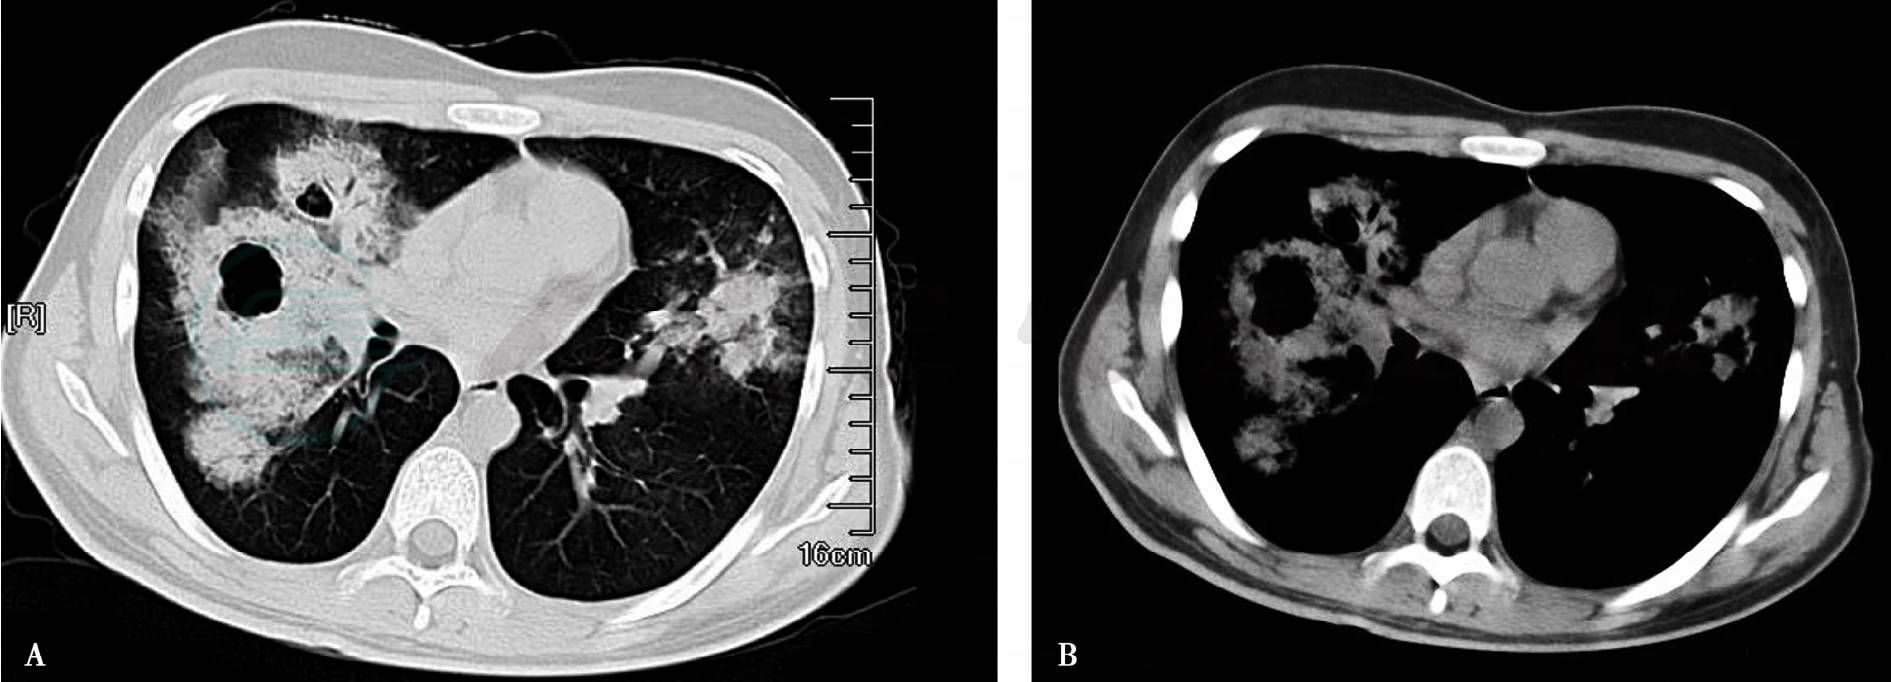

4.胸部CT(2009年12月28日,图1):右肺中叶及下叶内基底段可见大面积阴影,有多发空洞,部分密度较高,右肺下叶后外侧可见多发囊性空洞,左侧舌段高密度影。

图1 2009年12月28日胸部CT

重要的检查结果有五项:①末梢血白细胞总数正常、中性粒细胞百分比有增高;②胸部影像学示双肺多发浸润影伴有多发空洞;③动脉血氧分压降低;④便常规白细胞略增高,便球杆比正常;⑤痰涂片提示革兰阴性杆菌。结合患者的病史和体格检查结果,进一步支持感染性疾病——社区获得性肺炎(community acquired pneumonia,CAP)的诊断,目前病原学考虑革兰阴性杆菌感染可能性大。患者发病以来曾自行服用过吉他霉素等药,考虑可能因未能覆盖病原体,故未能奏效。动脉血氧分压降低和多发浸润影说明炎症已累及多肺叶并已影响到气体交换,因此患者有胸闷、低氧血症。进一步的处理应立即选择合适的抗感染药物进行治疗,其目的有二:①治疗感染;②通过治疗明确或修正诊断。